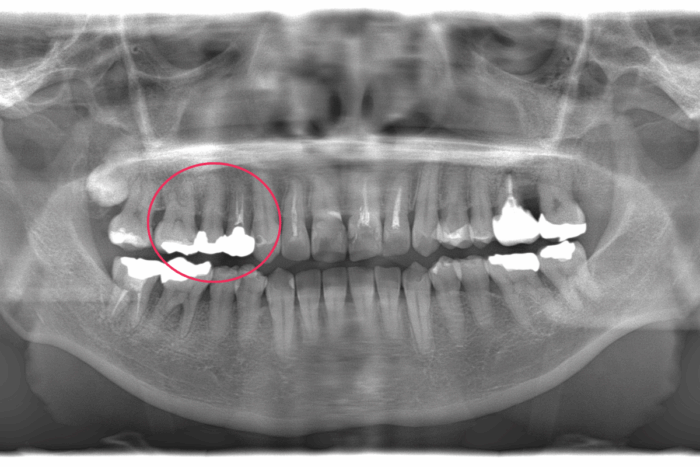

患者さま:30代女性/左上4・5・6番にメタルブリッジ

主訴:歯のガタつき・かみ合わせが反対

矯正治療のために上下左右4本抜歯する必要がありました。そのため、抜歯する歯のうち1本は、ブリッジを分割しポンティック部分(ブリッジの真ん中の人工歯のこと)を除去して代用しました。ワイヤー矯正で歯並びとかみ合わせを改善しました。

- 【症例詳細】

- 主訴:ガタガタと受け口が気になる

- 診断名:叢生・反対咬合

- 初診時年齢:32歳

- 使用装置:ホワイトワイヤー矯正

- 抜歯部位:上顎右側第二小臼歯、下顎右側第二小臼歯、下顎左側第一小臼歯

- 治療期間:2年7ヶ月

- 費用:¥750,000(税込¥825,000)

- リスク・副作用:痛み、歯根吸収、歯肉退縮、むし歯、後戻り